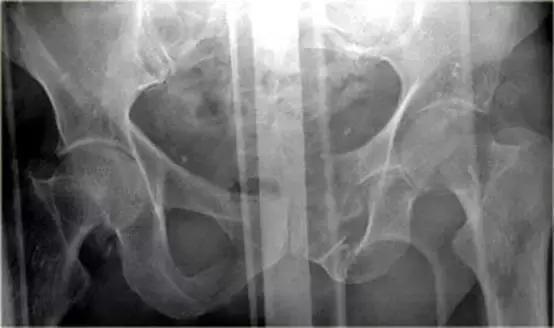

骨盆X线示耻骨骨折,膀胱区见游离骨片。

对骨盆外伤骨折病人应如检查?

该类病人存在盆腔动脉损伤及血肿形成,以及直肠、阴道、膀胱损伤的危险。

因此在常规CT(增强)检查之后需要加做膀胱造影 CT检查。

同一病人的CT常规增强检查

结果

有一个指向膀胱的骨盆骨折碎片。

膀胱直肠隐窝积液。

10%骨盆骨折伴有膀胱破裂。

最初认为膀胱破裂都是由骨盆骨折引起,但现在知道只有1/3的膀胱破裂是因为游离碎骨片造成的,另外2/3是由于剪切伤作用于膀胱造成破裂。